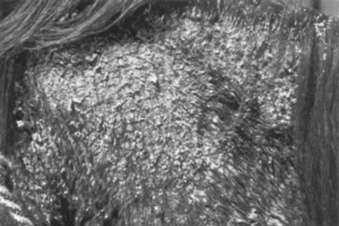

The disease is infrequently encountered, and there is no known breed predilection. Geldings may be at increased risk.287 The skin lesions typically are generalized scaling and crusting associated with varying degrees of alopecia (Fig. 40-20). Occasionally, the disease is focal or multifocal in distribution. Rarely, the skin lesions consist of nodules or large, tumor-like masses. The different types of skin lesions may coexist. In addition to skin lesions, the most frequent presenting complaints are weight loss, decreased appetite, and a persistent low-grade fever. Lung involvement is manifested by exercise intolerance, increased resting respiratory rate, and mild dyspnea.288-290 Although one report showed positive titers to Borrelia burgdorferi in three of four horses with equine sarcoidosis,291 a more recent report was unable to demonstrate the presence, using PCR and histologic stains, of any causative organism.287

image

Fig 40-20 Equine sarcoidosis (generalized granulomatous disease) in a horse. In addition to the scaling and crusting skin lesions, the horse has systemic involvement. (Courtesy Dr. Anthony Stannard.)

Diagnosis is by histopathology and ruling out infectious etiologies. The major histologic change is the presence of noncaseating granulomas consisting of aggregates of epithelioid cells and multinucleated giant cells. Neutrophils, lymphocytes, and plasma cells are present in small numbers. In the skin the granulomas tend to be located in the superficial portion of the dermis. Because of the small number of horses studied and the variability of clinical signs, response to therapy has not been well documented. A recent abstract reported that five of six horses did well and lived longer than 1 year with prednisolone treatment.292 Another extensive review showed that some horses did well on corticosteroid therapy (usually at doses approximating those used to treat pemphigus and other autoimmune skin diseases); gastrointestinal involvement was a sign of poorer prognosis.287